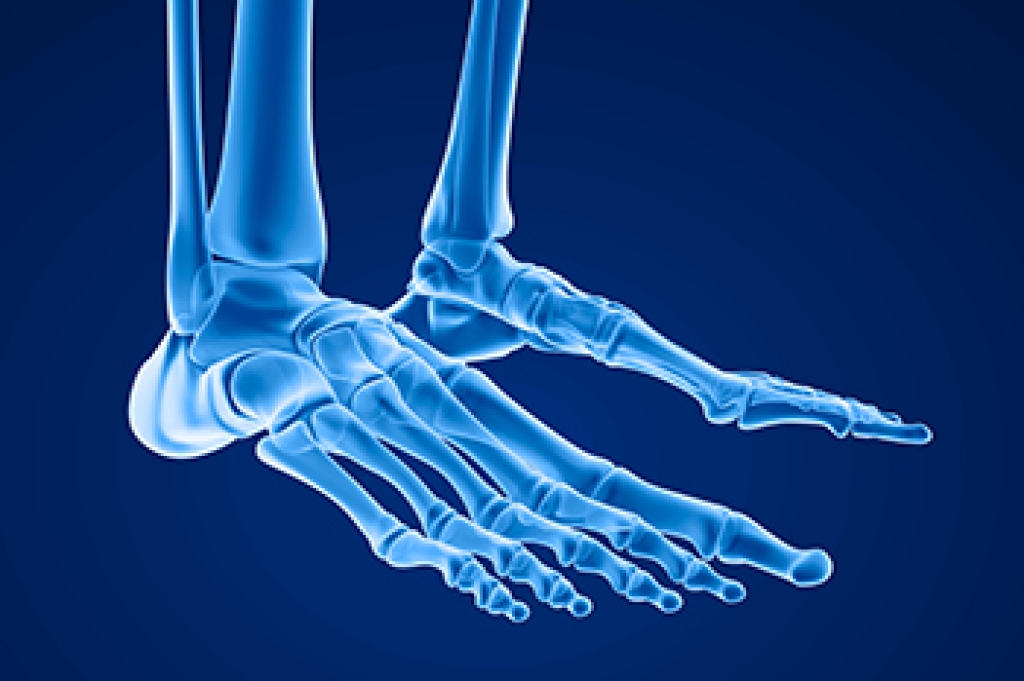

The feet and ankles are complex structures. The 26 bones, several muscles, tendons, and ligaments work together in harmony to achieve balance and mobility. There are three bones that are located in the ankle joint. These enable up-and-down movement, causing flexibility in the foot. Additionally, there are also three bones that are located in the foot and are known as the hindfoot, midfoot, and forefoot. There is soft tissue and cartilage between the bones that hold them together which absorbs the impact of the body and provides stability to the body. There are 20 muscles that are found in each foot, and each group of muscles is responsible for various functions. The toes can lift and curl by using smaller muscles, and the peroneal tibial muscle controls the movement to the outside of the ankle. If you would like additional information about how the components of the feet work together, it is suggested that you seek the counsel of a podiatrist who can provide you with interesting foot facts.